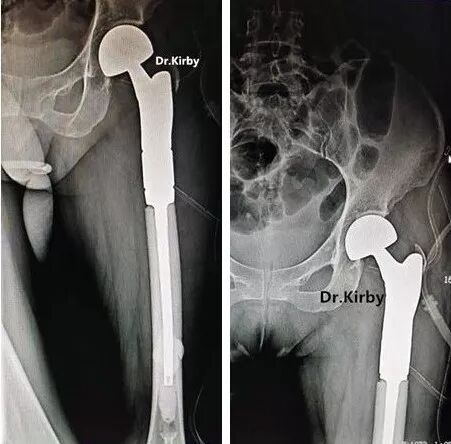

患者沈先生,20年前因外傷致左股頸骨折,在當(dāng)?shù)啬翅t(yī)院治療,治療后仍不能正常行走。20年間患者就診于嘉興、杭州、上海各大醫(yī)院進行治療,均建議手術(shù),費用約15萬。

后經(jīng)人介紹沈先生找到了省級知名骨科專家、邦爾骨科集團首席專家、嘉興邦爾骨科醫(yī)院院長趙凱教授。經(jīng)過檢查,趙凱教授為其進行了“人工髖關(guān)節(jié)翻修術(shù)”,術(shù)后恢復(fù)良好,疼痛解除,而且實際費用不到上海、杭州的三分之一。

術(shù)前顯示:髖關(guān)節(jié)置換術(shù)后假體脫位

術(shù)后假體位置良好